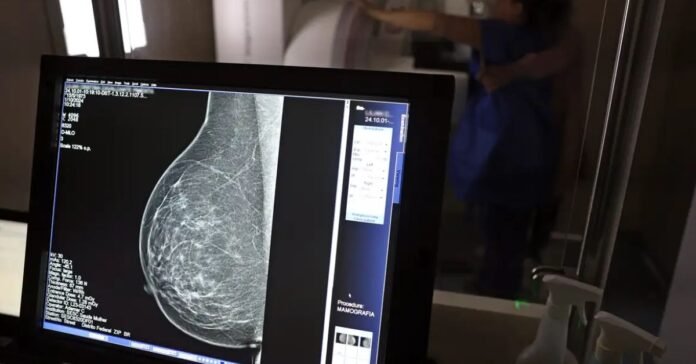

O Ministério da Saúde passou a recomendar o acesso a mamografia, via Sistema Único de Saúde (SUS), para mulheres de 40 a 49 anos – mesmo que não haja sinais ou sintomas de câncer de mama. De acordo com a pasta, a faixa etária concentra 23% dos casos da doença, e a detecção precoce aumenta as chances de cura.

Até então, a orientação era que o exame fosse feito a partir dos 50 anos.

A medida faz parte de um conjunto de ações anunciadas nesta terça-feira (23) voltado para a melhoria do diagnóstico e da assistência. A recomendação para mulheres a partir dos 40 anos é que o exame seja feito sob demanda, em decisão conjunta com o profissional de saúde.

“A paciente deve ser orientada sobre os benefícios e desvantagens de fazer o rastreamento. Mulheres nesta idade tinham dificuldade com o exame na rede pública de saúde por conta da avaliação de histórico familiar ou necessidade de já apresentar sintomas”, informou o ministério em nota.

As mamografias via SUS em pacientes com menos de 50 anos, de acordo com a pasta, representam 30% do total, o equivalente a mais de 1 milhão apenas no ano de 2024.

Outra medida anunciada é a ampliação da faixa etária para o rastreamento ativo – quando a mamografia é solicitada de forma preventiva a cada dois anos. A idade limite, até então, era 69 anos. Agora, passa a ser 74 anos. Dados do ministério revelam que quase 60% dos casos de câncer de mama estão concentrados entre 50 e 74 anos.

“A ampliação do acesso à mamografia aproxima o Brasil de práticas internacionais, como as adotadas na Austrália, e reforça o compromisso em garantir diagnóstico precoce e cuidado integral às mulheres brasileiras. O câncer de mama é o mais comum e o que mais mata mulheres, com 37 mil casos por ano”, reforçou a pasta.

Os números mostram que, em 2024, cerca de 4 milhões de mamografias para rastreamento e 376,7 mil exames diagnósticos foram realizados no SUS.